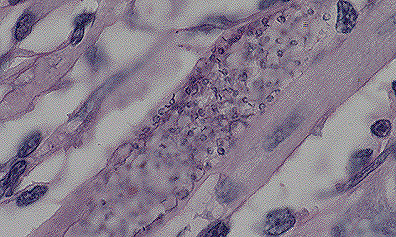

Necrotizing colitis with intraepithelial coccidial schizonts in a calf. (40X, HE, 110K)

Iintraepithelial coccidial schizonts in the colonic epithelium of a calf. (100X, HE, 114K)

Contributor's Diagnosis and Comments: Colitis, fibrinopurulent, diffuse, severe, with intra-epithelial coccidia.

Microscopic lesions vary in appearance among the histological slides. In the section of colon examined, clumps of fibrin containing cellular debris and inflammatory cells are adhered to the mucosa. Most crypt epithelial cells contain schizonts, gamonts, or developing oocysts. Many intestinal crypts are distorted or have been destroyed as a result of coccidial infection. Erosion and ulceration of the mucosa have occurred. A lymphoplasmacytic inflammatory reaction is present in the lamina propria.

The most likely etiologic agent is Eimeria zuernii which is one of the most common and pathogenic coccidia of ruminants. The other is E. bovis. Life cycles of both agents are similar. Large schizonts typical of either E. bovis or E. zuernii were not observed in multiple sections of jejunum and ileum examined. Eimeria bovis infects endothelial cells in lacteals of the jejunum located several meters anterior to the ileocecal valve; whereas, E. zuernii schizonts are found in the lamina propria of the terminal ileum. Secondary schizonts and gamonts of E. zuernii develop in the glands of the cecum and colon but not terminal ileum.

AFIP Diagnosis: Colon: Colitis, necrotizing, subacute, diffuse, moderate, with erosions, and myriad intracellular coccidia, Hereford-cross, bovine, etiology consistent with Eimeria sp.